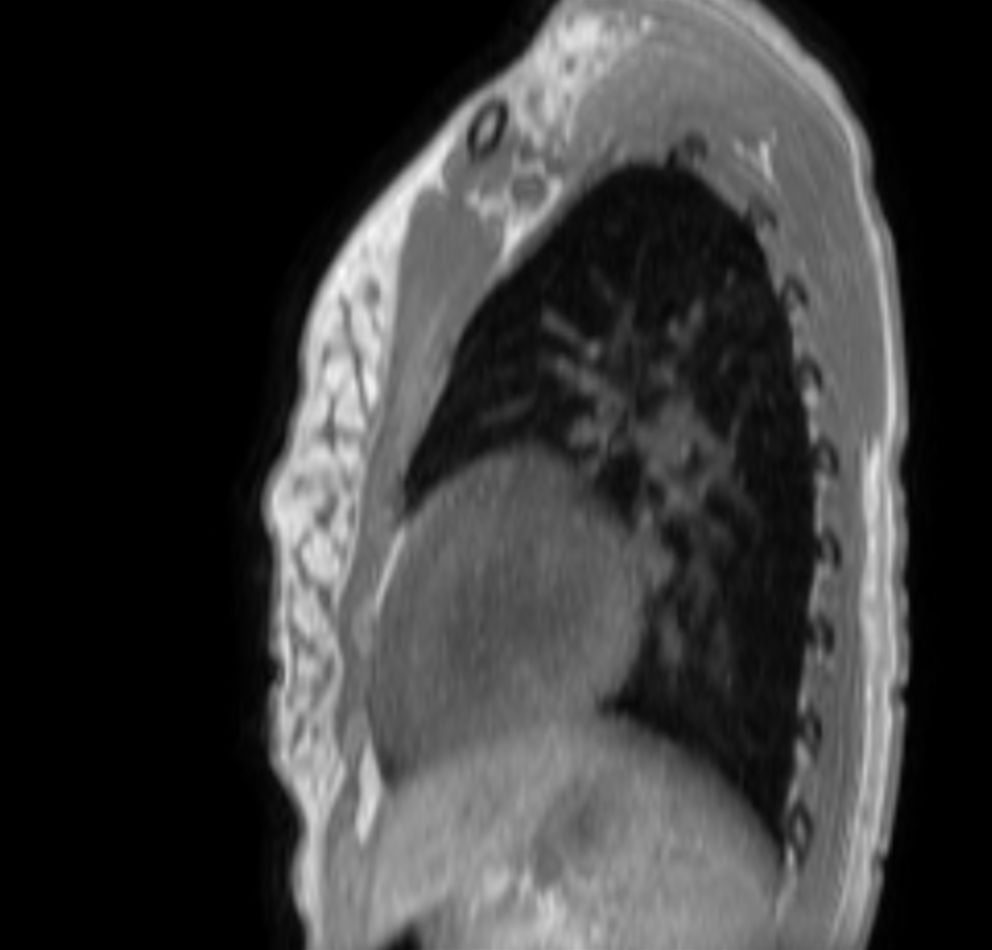

T2w TSE - MultiVane XD